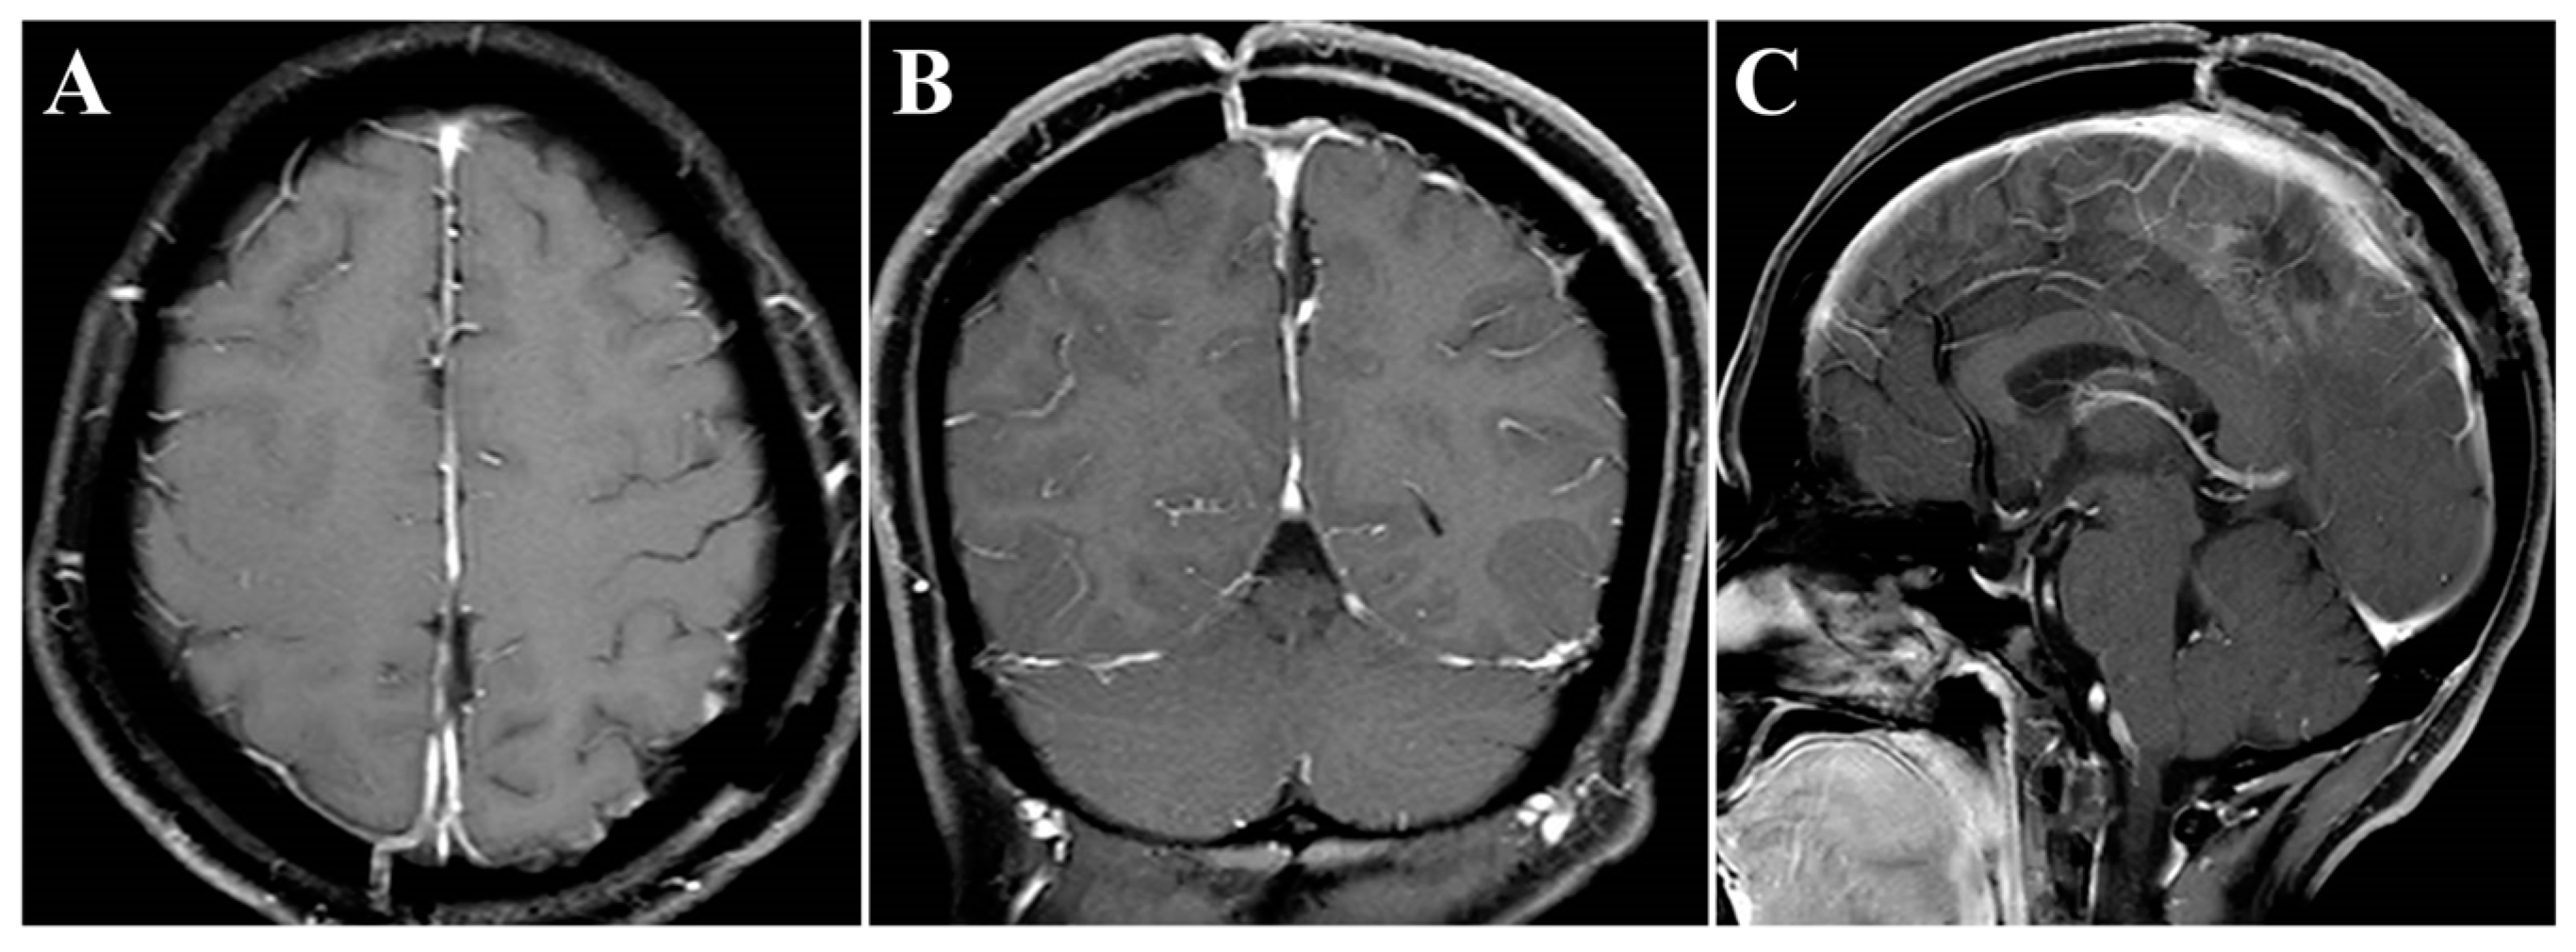

In November 2020, a 55-year-old female was admitted to our hospital and presented with a 6-month history of headache. On general physical examination, she presented with no other remarkable symptoms. MRI revealed a mass approximately 2.9 × 4.2 × 4.1 cm in size, with an attachment in the middle-third of the falx (Figure 1A–C). This parafalcine lesion was mainly extended to the left, with no significant perilesional edema. Neuronavigation showed two drainage veins above the tumor (Figure 1D), which is important for formulating the surgical strategy. Consequently, FM was diagnosed, and surgery was scheduled using the ipsilateral interhemispheric approach to access and remove the tumor using endoscopy through the safe zone between the two veins.

Figure 1.

Preoperative imaging and intraoperative navigation showed a middle-third falcine meningioma. (A–C) Contrast-enhanced MRI axial (A), coronal (B), and sagittal (C) images. (D) Neuronavigation (3D image) demonstrated two drainage veins above the tumor (white arrow).

Noteworthily, in this case, there were two critical draining veins above the tumor, which increased the difficulty of tumor resection. However, we successfully removed the tumor using the endoscopic ipsilateral interhemispheric approach without any venous complications during or after surgery. Additionally, the presence of ipsilateral brain edema can narrow the entry corridor, representing a key concern of the ipsilateral interhemispheric approach. However, this concern can be overcome by using the gravity-assisted technique to gain more operating space, which is sufficient to allow safe and effective removal of the tumor using the endoscopic approach [6]. In this case, the main considerations for the use of the retractor were the presence of two critical draining veins above the tumor and the absence of severe ipsilateral brain edema. Gravity-assisted lateral positioning may increase tension in the veins, leading to injury, while the retractor is more controllable to keep brain retraction to a minimum. In other situations, such as the presence of severe ipsilateral brain edema or the absence of interference of draining veins, we would implement the gravity-assisted technique to extend the lateral corridor diameters. In the current case, postoperative MRIs showed that the overlying eloquent cortex returned to its original morphology (Figure 4).